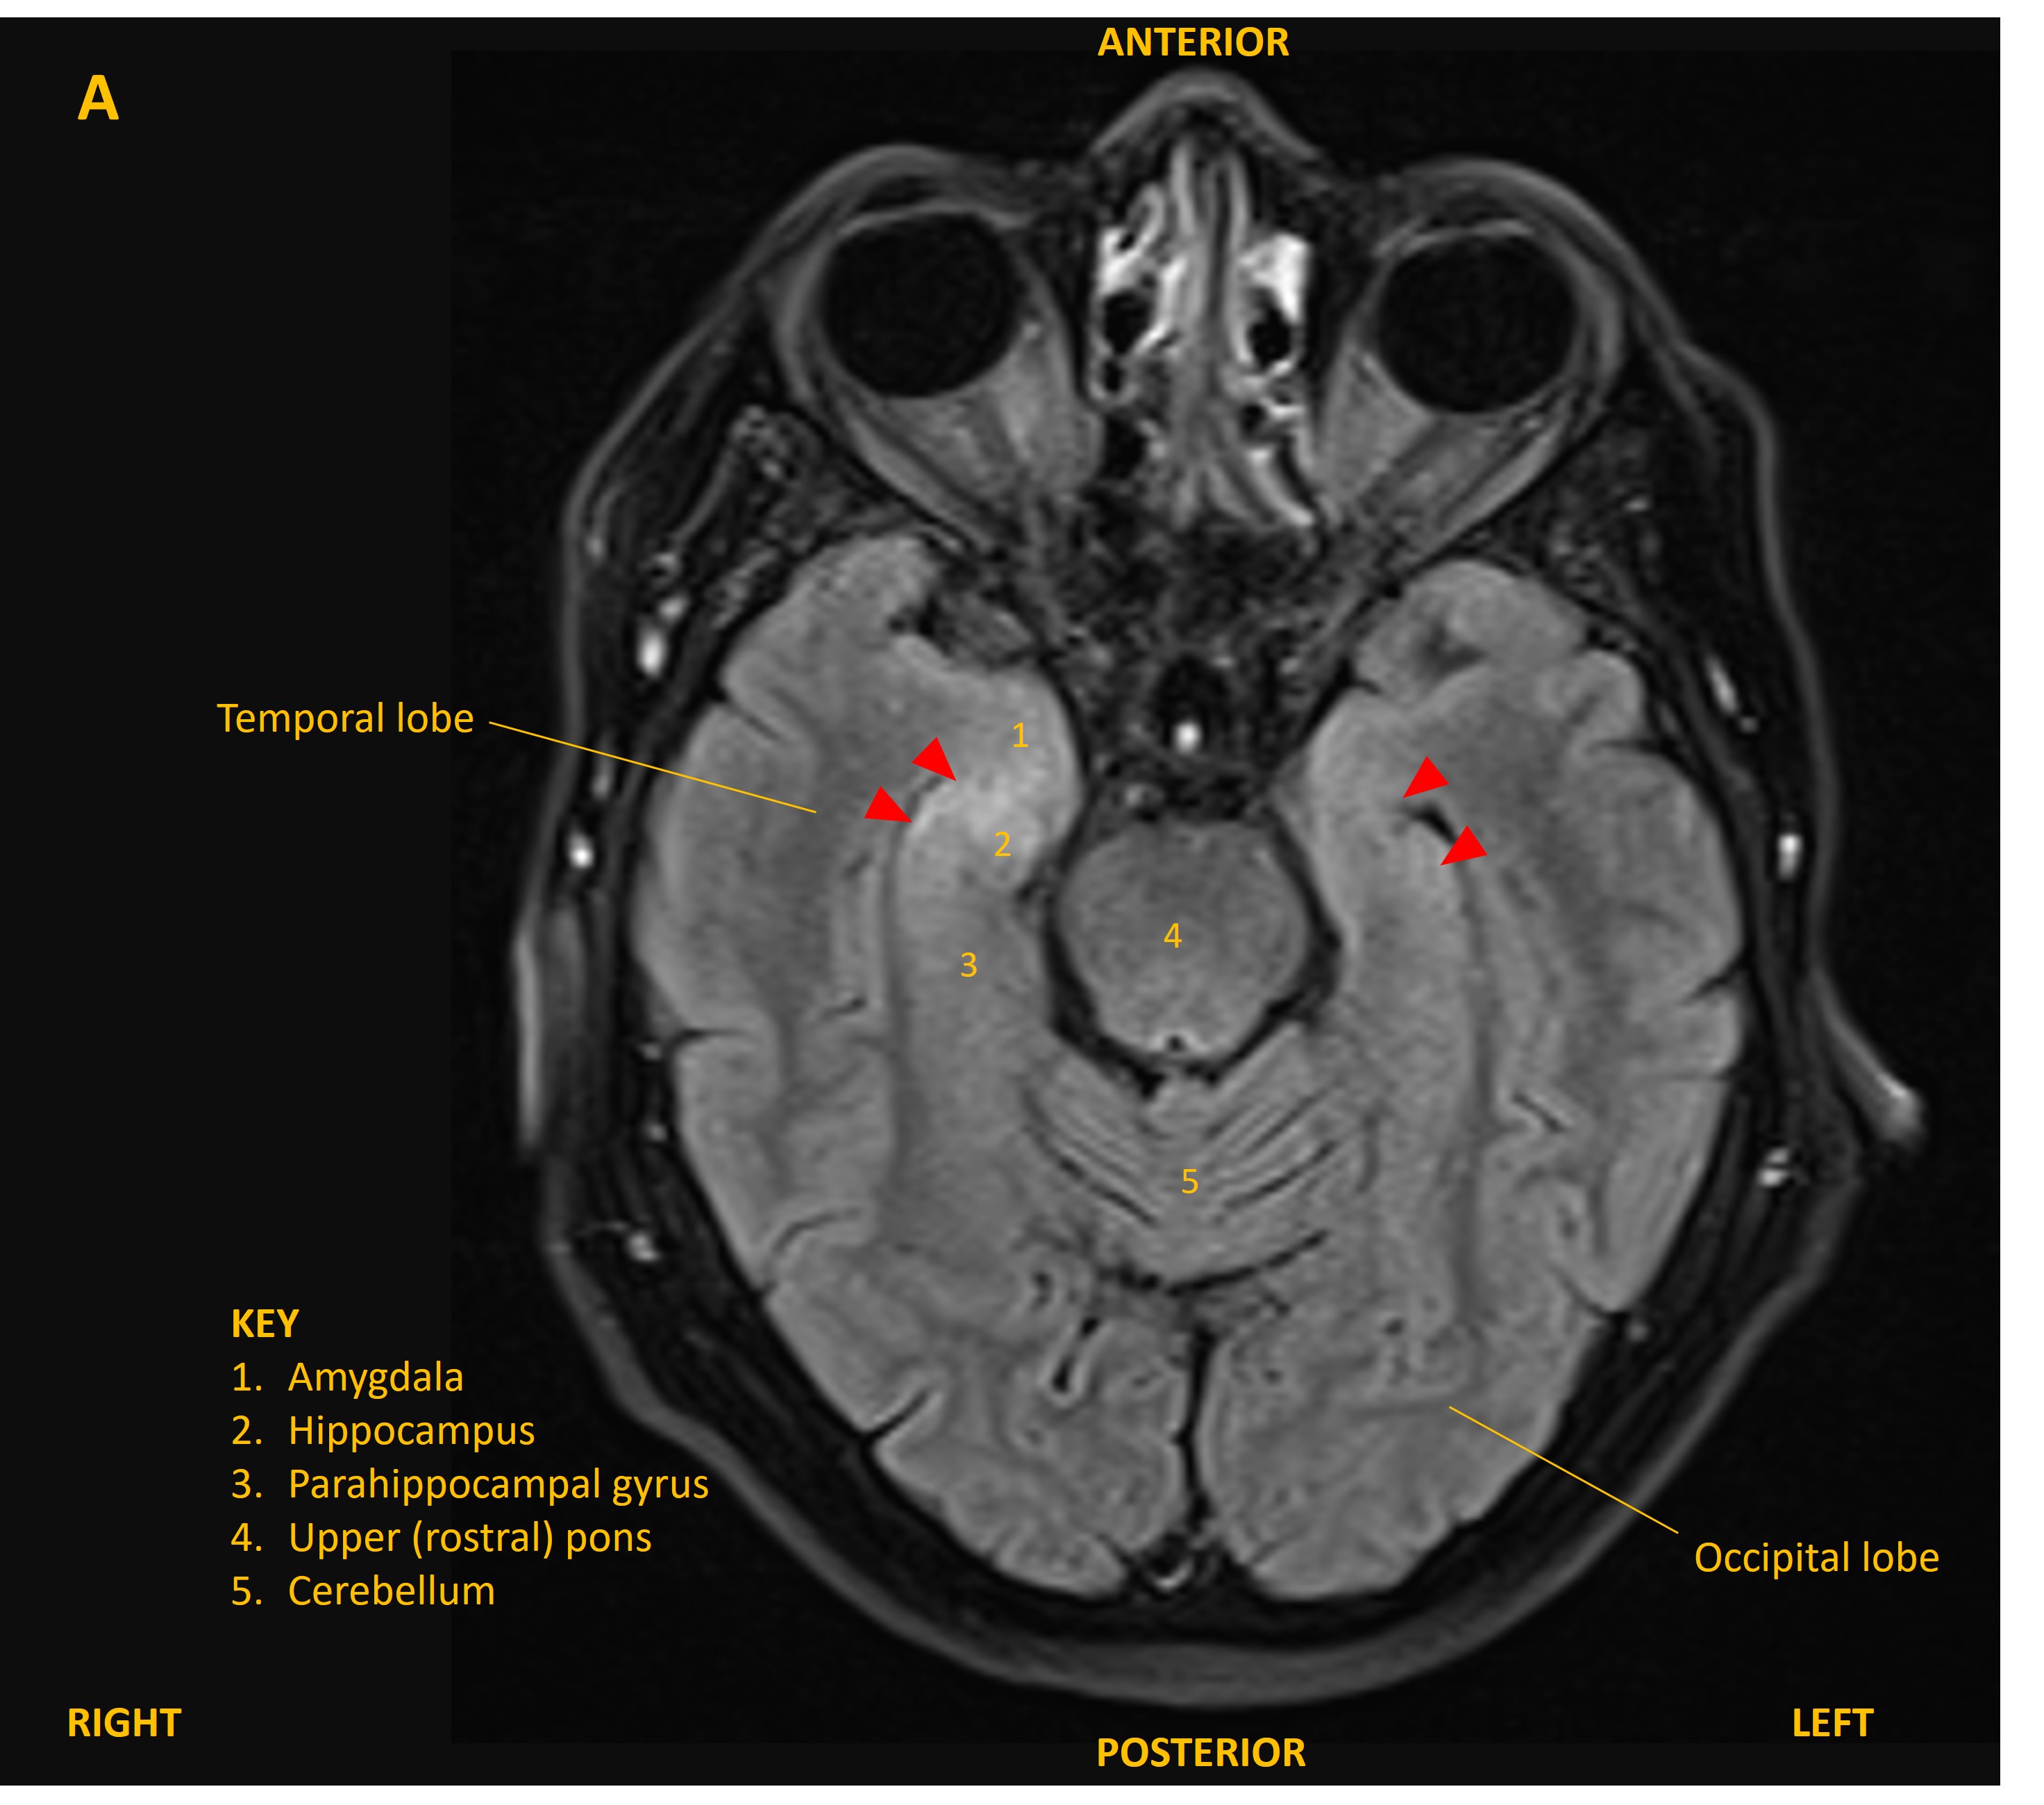

The patient was admitted and was treated empirically with aciclovir for possible viral encephalitis until a lumbar puncture showed normal CSF cell counts, glucose, and protein, and viral PCR was negative. An MRI brain showed bilateral changes on FLAIR confined to the mesial temporal lobes, involving the hippocampi and other limbic structures (figure A and B, red arrowheads). This was suggestive of limbic encephalitis.

MRI A